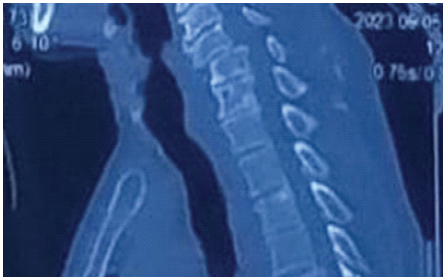

A computed tomography scan depicted an anterior dislocation of C5 over C6 with bilateral locked facets (Fig. 3).

Figure 3: Computed tomography scan showing anterior dislocation of C5 over C6 with bilateral locked facets.